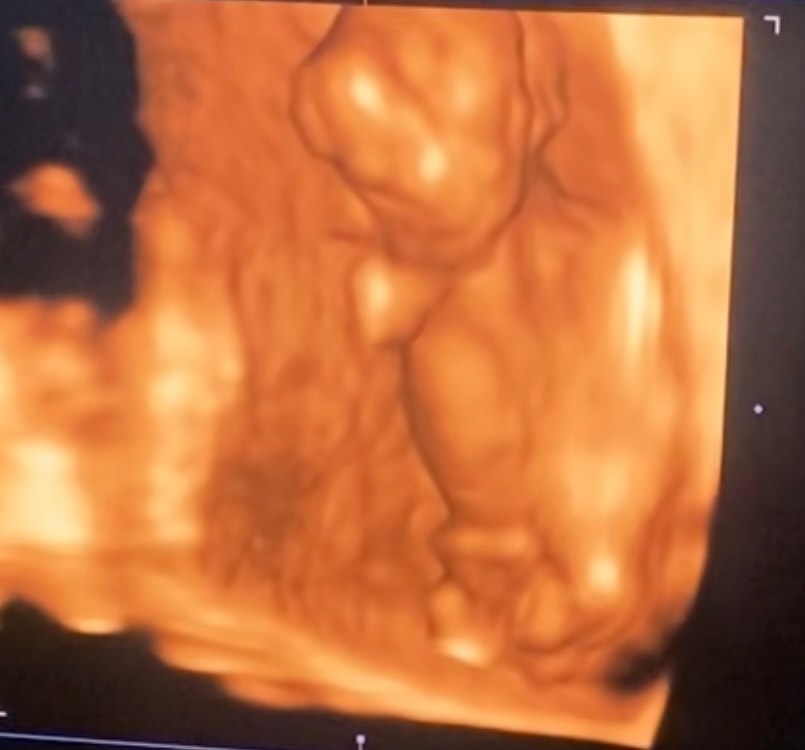

Я беременна,уже 13 недель,на 12-ой неделе врач осмотрел и сказал,что будет девочка,но засомневался,сказал что придёте на 20-ой неделе точно скажем.. Сможете по фото узи сказать пол? Заранее спасибо🫶🏻